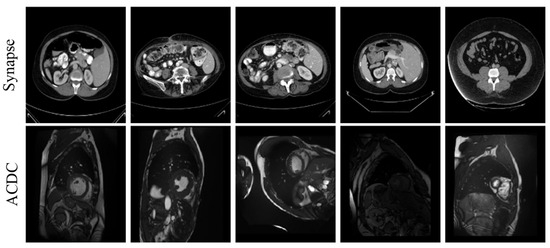

To evaluate the performance of the proposed approach, we use two publicly accessible medical image segmentation datasets—the Synapse dataset and the ACDC dataset. See Table 1 and Figure 5 for details.

Here are 30 abdominal CT scans in the Synapse dataset. Annotations of eight organs—liver, pancreas, spleen, stomach, right and left kidneys, aorta, and gallbladder—are included in the dataset, which consists of 3779 axial slices of abdominal CT scans. Every slice is 512 × 512 pixels in size. In this case, with reference to the TransUNet literature, the slices from 18 cases were used as the training set, and the remaining 12 cases were reserved for testing and evaluation.

Each of the 100 sets of cardiac magnetic resonance images in the ACDC dataset was annotated by a specialist with knowledge of the left atrium, right ventricle, and myocardium. In this investigation, we adhered to the data partitioning approach utilized in TransUnet, segregating the dataset into 70 cases for training, 10 for validation, and 20 for testing.

Figure 5. Pictures of the selected datasets are shown.